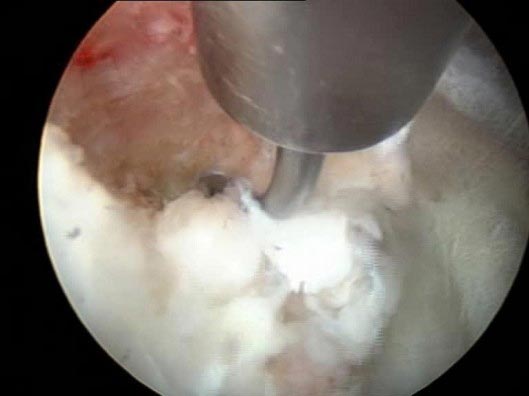

Ευμέγεθες τεμάχιο δισκικού υλικού αφαιρεθέν με Ενδοσκοπική Χειρουργική (

Ενδοσκοπική Δισκεκτομή) μέσα από το δεξί μεσοσπονδύλιο τρήμα Ο4-Ο5

2) Ενδοσκοπική αφαίρεση ευμεγέθους τεμαχίου δίσκου Ο4-Ο5 δεξιά με Ενδοσκοπική Χειρουργική

Ενδοσκοπική δισκεκτομή)